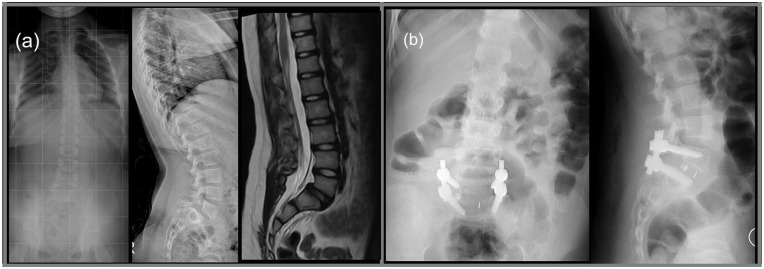

Abstract Image